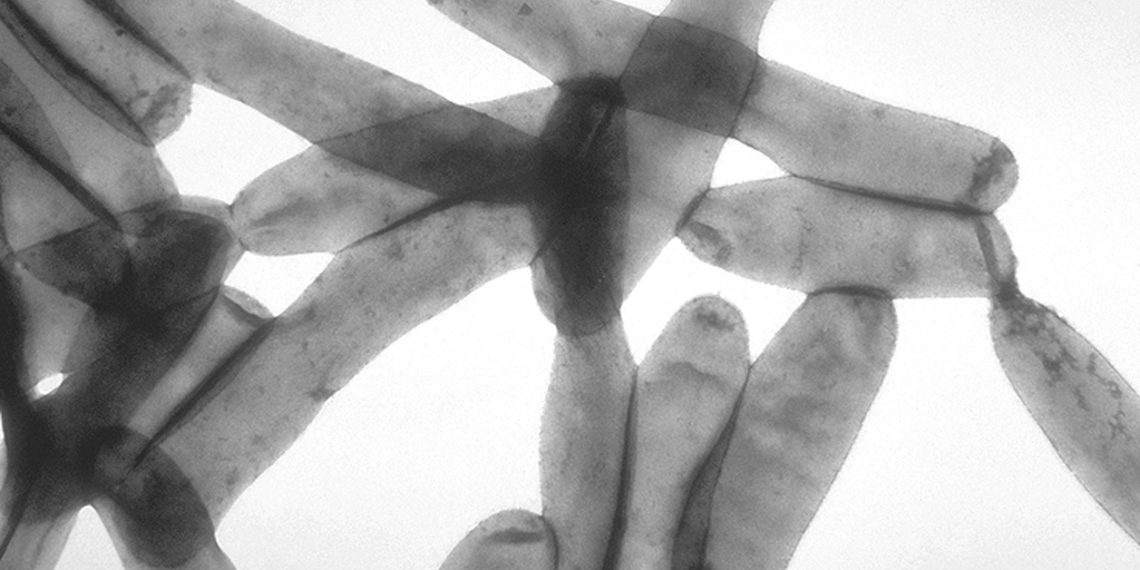

This pathogenic bacterium, Legionella Pneumophila has 300 toxins that infect humans. But once the bacteria is inhaled, legionella enters the lungs and infects human cells and causes pneumonia.

Some researchers from EMBL Grenoble and Goethe University, Frankfurt studied the toxin SidJ in detail. And it is a vital toxic protein of Legionella. It injects into the human cytoplasm and enables the successful infection and replication of the bacteria.